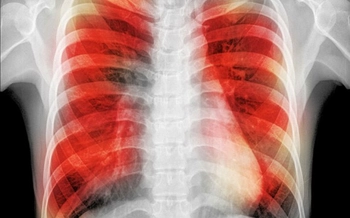

• Study Explains Increased Risk of TB for Smokers

'Clogged-up' immune cells are to blame.

• A ‘Game-Changer’ – Latest TB Research From Trinity

New findings especially useful for drug-resistant forms of the disease